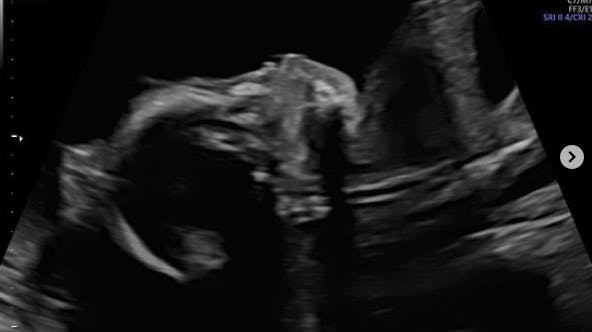

På Instagram fortæller den unge mor, at hun er gravid i 25. uge nu, og at hun i uge 23. fandt ud af, hendes lille pige ikke ville klare den.